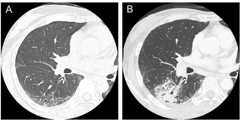

Computed tomography scans in a patient with systemic sclerosis:

(A) Interstitial lung disease was observed in lower lobes in a 47-year-old patient.

(B) Squamous cell lung cancer occurred in the area of interstitial lung disease in a 50-year-old patient.